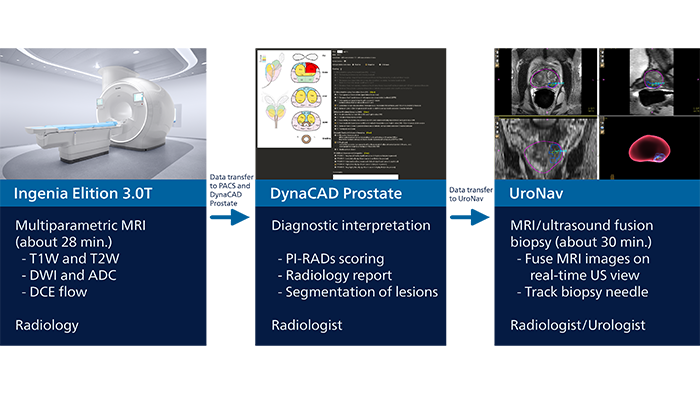

Moving from TRUS biopsies to multiparametric MRI and targeted biopsies guided by fused MRI/ultrasound images is benefiting high-risk prostate cancer patients at WellSpan York Hospital in York, Pennsylvania. Dr. Edward Steiner has collaborated with urologists to set up an alternative patient pathway for prostate carcinoma diagnosis through the use of multiparametric MRI and MRI/ultrasound fusion for targeted biopsies. Particularly when a patient with clinically significant prostate carcinoma has had multiple negative TRUS biopsies before, this targeted procedure can assist urologists to quickly make a confident diagnosis, and allows patients to start therapy as soon as possible. This may be life-changing for the patient.

The use of MRI has significantly improved capabilities in prostate cancer diagnosis, according to Dr. Steiner. “Multiparametric prostate MRI allows us to look at three parameters to build our diagnosis on: conventional T1 and T2 signal intensity, diffusion-weighted imaging and ADC map, as well as dynamic flow imaging, to define the highest probability of prostate carcinoma.” The standard PI-RADS1 system is then used to grade lesions based on the MRI findings. For PI-RADS 1 and 2, clinically significant cancer is (highly) unlikely. Intermediate PI-RADS 3 lesions represent a kind of diagnostic “gray area” – these lesions may become PI-RADS 4 lesions if they demonstrate a hypervascular tumor flow pattern or depending upon index of suspicion. PI-RADS 4 and 5 lesions have a statistically high chance of being a clinically significant prostate carcinoma and should be biopsied. Once biopsy is performed, the pathologists characterize the biopsy samples with either a Gleason score or an ISUP grade group.2 “Contrary to other techniques, MRI allows for examination of the entire prostate gland with high soft-tissue contrast,” says Dr. Steiner. “Multiparametric MRI allows us to identify suspicious lesions and give these a PI-RADS score. For high-risk lesions, a biopsy can then be performed, guided by MRI images that are fused with ultrasound images in real time. This allows targeting of the lesions that were identified before.”

“I perform this interrogation using DynaCAD prostate, which also provides an easy way to determine PI-RADS score and create the report for the urologist.”

Dr. Steiner explains how a “blind” ultrasound biopsy may lead to a negative result, even when a tumor is present. “In a non-targeted biopsy guided by ultrasound, you see the needle and the confines of the prostate, but cannot see the tumor. So, when trying to get 12 cores as evenly distributed as possible, the tumor may still be missed, particularly when it is in the anterior gland, low in the apex or in other regions generally not easily biopsied by ultrasound.” This is why Dr. Steiner has implemented a pathway where the MRI images can also be used to guide the biopsy. He uses an MR/ultrasound fusion guided biopsy device, UroNav, which fuses pre-biopsy MRI images of the prostate with real-time ultrasound images during transrectal biopsy, for excellent delineation of the prostate and suspicious lesions, as well as clear visualization of the biopsy needle path. “I felt strongly that urologists are used to doing free-hand biopsies – their brain and hand are very used to manipulating the probe,” says Dr. Steiner. “What UroNav offers is no change in that workflow; it takes the diagnostic MRI images and the localized, segmented lesions and adds tracking and navigation to fuse that with the live ultrasound images. In this way, the MRI images can be used for targeting the lesion when performing the biopsy. The UroNav navigation sensor is mounted on the TRUS probe*, so for urologists the manipulation is similar to what they were used to.” “This process allows us to perform focal biopsies of suspicious areas based on PI-RADS categories that indicate the probability of an underlying potential malignancy,” says Dr. Steiner.

“I partnered with one of our local urology groups and we jointly did the first ten MRI fusion biopsies in our operating room, which gave us both experience as well as leadership. Having the UroNav capability added ‘GPS navigation’ to the urologist’s normal workflow and we could perform targeted biopsy. And I already owned DynaCAD, from which data could directly be imported to UroNav. It was a great win-win,” Dr. Steiner says.

“DynaCAD allows me to easily import the images into UroNav for eventual biopsy,” he says. “The decision for biopsy is taken after interpreting the MRI. So, if I don’t use DynaCAD/UroNav I would have to import the data into another modality and literally need to redo all of my work.”